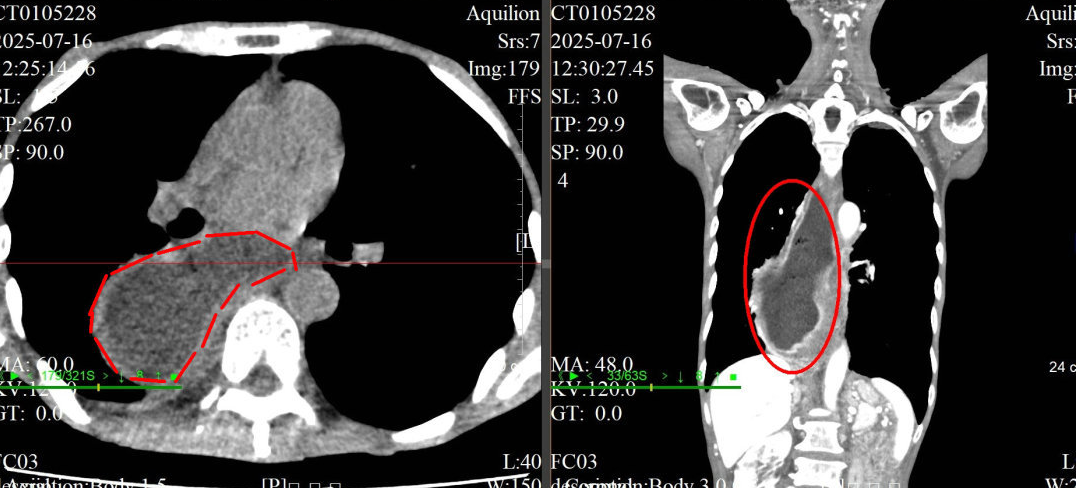

CT水平面和冠状面显示,老伯的食管严重扩张,形成了巨大的憩室,已经不是正常的“管状”了。